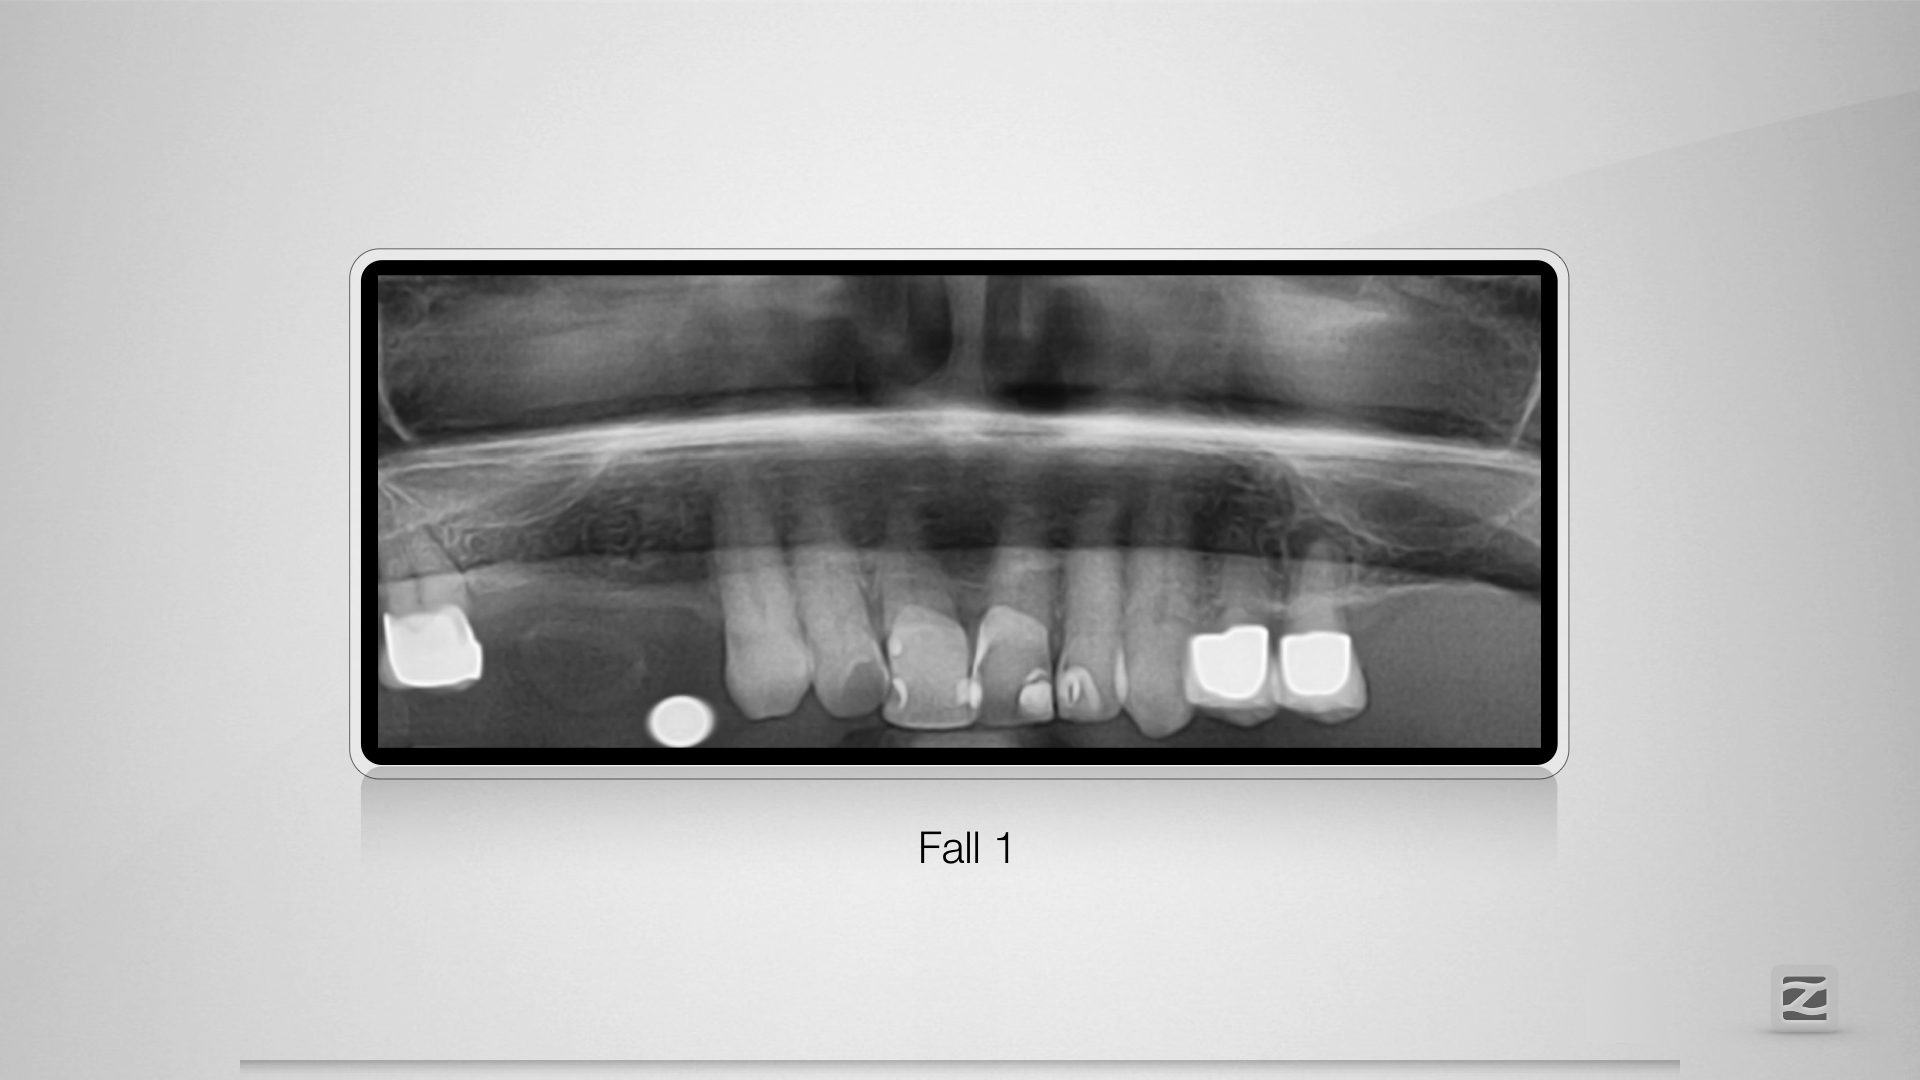

PerforationD.001

Übermut tut selten gut.